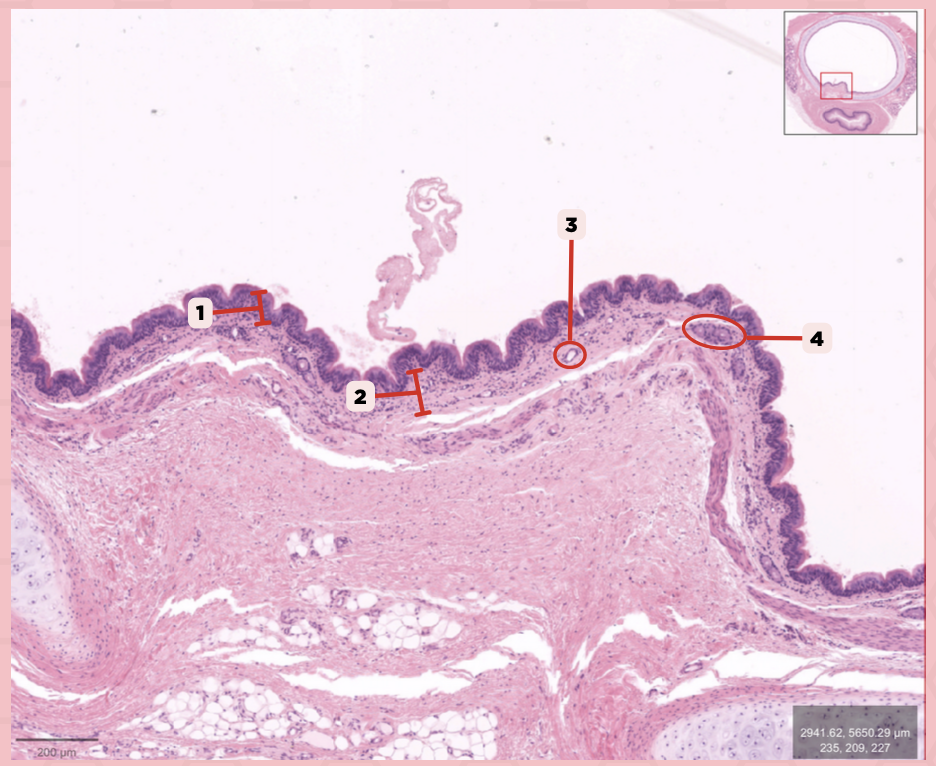

Identify the structure labeled as 1.

Nasal septum

Identify the structure labeled as 2.

Nasal cavity

Identify the structure labeled as 3.

Hard palate

Identify the structure labeled as 4.

Mucosal Associated Lymphoid Tissue (MALT)